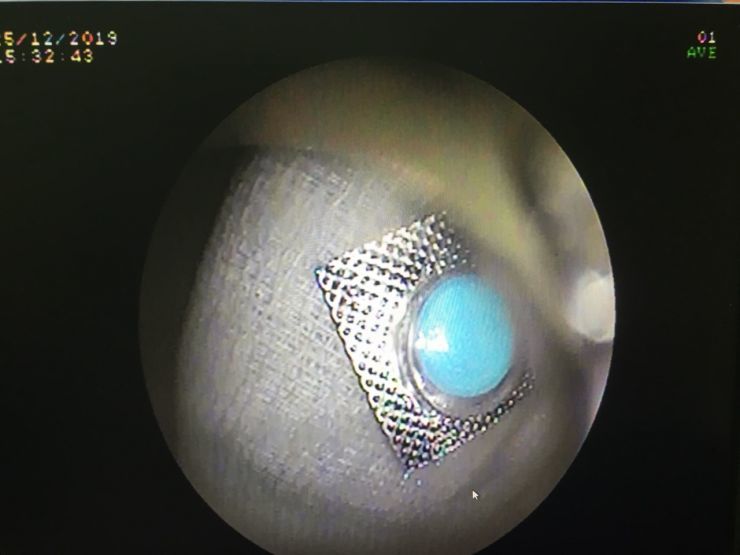

Lúc tiếp nhận, Khoa Cấp cứu đã tiến hành đưa bệnh nhân đến phòng Nội soi để tiến hành nội soi. Bác sĩ chẩn đoán cho thấy dị vật viên thuốc còn nguyên vỏ kích thước 9 x 9mm, hình vuông cạnh sắc bén như dao ở thực quản đoạn giữa, có nguy cơ gây thủng thực quản vào trung thất có thể dẫn đến tử vong.

Vỏ thuốc mắc kẹt ở thực quản của người phụ nữ. Ảnh:BSCC

Để tránh nguy cơ viên thuốc sặc vào phổi, ê-kíp phải tiến hành gây mê nọi soi gắp dị vật để an toàn cho bệnh nhân. Bác sĩ đã tiến hành chụp dị vật bằng silicon bao lại để tránh chảy máu và thủng thực quản khi kéo viên thuốc ra ngoài.